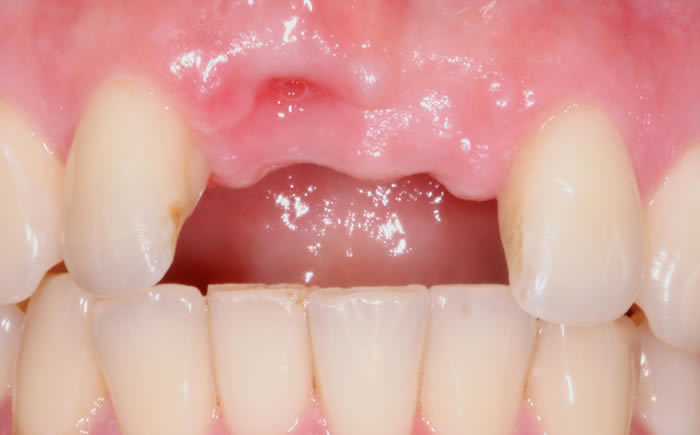

Missing upper front tooth replaced by dental implant and crown